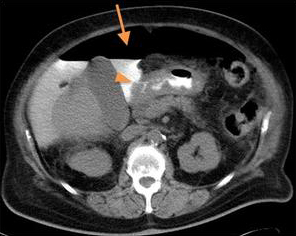

Ulcere gastrique perfore . Fleche jaune c'est espace gazeuse

peritoneale ( free air ) , triangle jaune c'est la cite duodenum en

perfore .